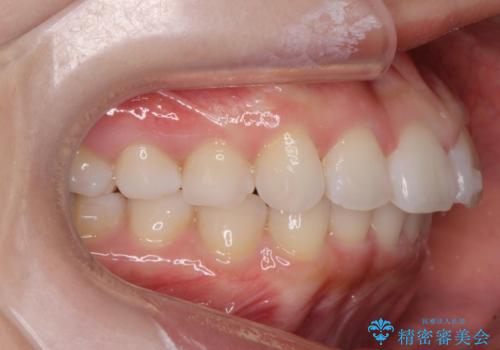

噛み合わせを確認したところ上の歯が全体的に前にある状態でした。

1 上の奥歯を後ろに引き噛み合わせを合わせて全体的に矯正を行う。(費用と期間がかかる)

2 前歯だけガタつきを並べる(全体矯正より費用が安く、短時間で終わる 奥歯の噛み合わせは変化しない)

患者様は2のプランを選ばれたのでインビザラインモデレートで治療を行いました。

ガタつきがなくなり満足して頂けました。